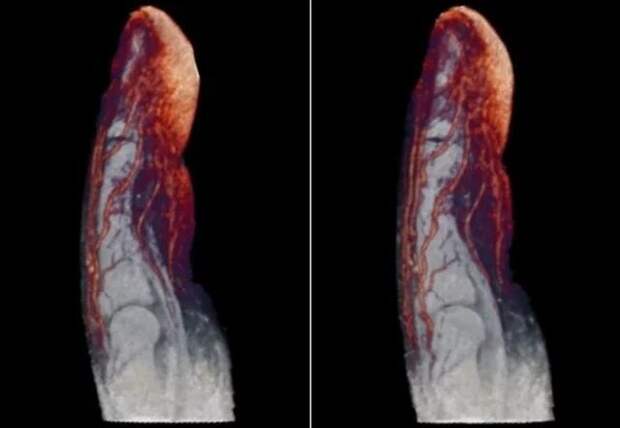

Травма головы  Кровеносные сосуды в пальце

Кровеносные сосуды в пальце  Компьютерная томография человека, который вез внутри себя контрабанду